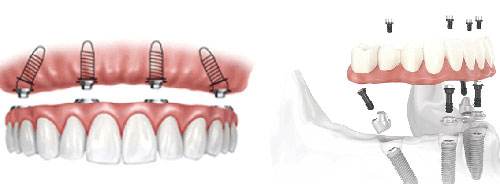

廊坊圣洁口腔数字化种植技术,即刻种牙,即刻进食

当天种牙、当天戴冠,All-on-4即拔即种,当天享受美食,避免了传统种植手术前后需半年到1年治疗期和多次受创过程,并极大地缩短患者缺牙时间,减轻缺牙痛苦。 》》》相关阅读:廊坊圣洁口腔医院ALL-on-4种植技术